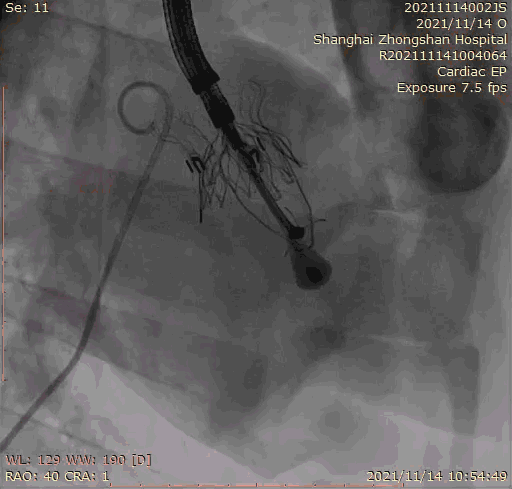

上海中山醫院葛均波院士、錢菊英院長、周達新教授、潘文志教授、潘翠珍教授、李偉教授共同完成此次臨床前研究。 術後葛均波院士對Lux-Valve Plus的器械操作效能給予了高度評價,DSA和超聲影像也顯示出在本次研究中Lux-Valve Plus的安全性和有效性俱佳。

本次臨床前研究經右側頸靜脈置入LuX-Valve Plus輸送系統可調彎鞘管,在DSA及超聲引導下將人工三尖瓣瓣膜植入到原有三尖瓣位置,利用獨特的錨定科技將人工瓣膜支架固定在預定的位置。